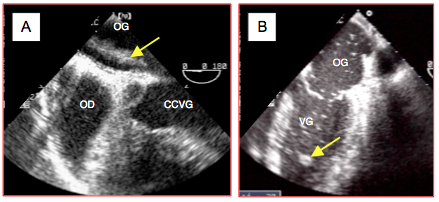

Figure 27.77 : Risque embolique dans l’appendice auriculaire gauche (AAG). A: thrombus dans l'AAG après un remplacement mitral avec une prothèse mécanique. B: contraste spontané dans l'AAG. C: Thrombus à l'entrée de l'AAG lors d'une défaillance ventriculaire gauche sous assistance mécanique (vue 2-cavités). D: Le même cas en reconstruction tridimensionnelle.

Figure 27.78B : Thrombus auriculaire gauche chez un patient sous assistance ventriculaire, en vue 2D 4-cavités haute et en vue 3D.